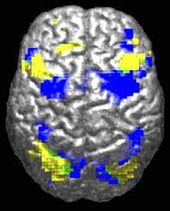

Autistic individuals tend to use different areas of the brain (yellow) for a movement task compared to a control group (blue).

Autistic individuals tend to use different areas of the brain (yellow) for a movement task compared to a control group (blue). 2.Autism affects the amygdala, cerebellum, and many other parts of the brain.

Autistic individuals tend to use different areas of the brain (yellow) for a movement task compared to a control group (blue). 2.Autism affects the amygdala, cerebellum, and many other parts of the brain.